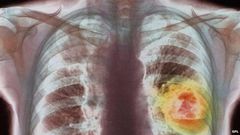

Nivolumab stops cancerous cells hiding from the body's own defences, leaving the cancer vulnerable to attack.

A "milestone" trial has shown that a lung cancer therapy can more than double life expectancy in some patients.

Nivolumab, one of a suite of drugs called "checkpoint inhibitors" being developed by pharmaceutical companies stops cancers from turning off the immune system so the body can keep on attacking the tumour.

According to BBC, people on standard therapy lived for another 9.4 months at this stage, but those taking Nivolumab lived for 12.2 months on average.

However, some patients did spectacularly well. Those whose tumours were producing high levels of PD-L1 lived for another 19.4 months.